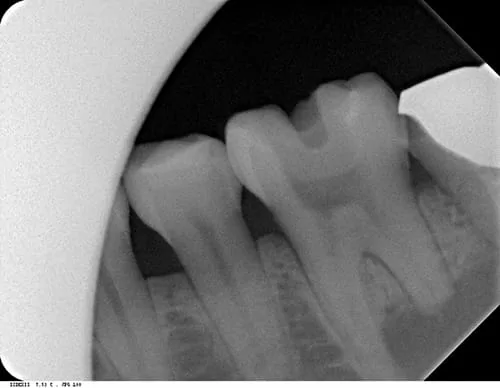

(2) 根尖X光片

術前 (左下第一大臼齒)